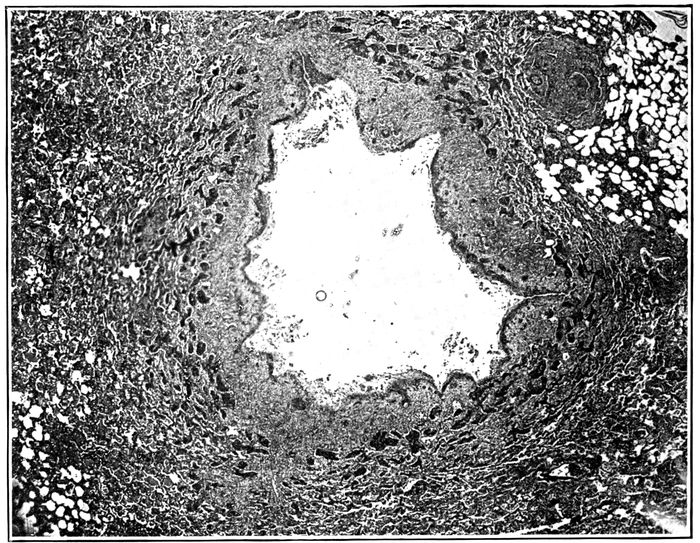

10. Interstitial suppurative pneumonia; interstitial septa are the site of suppuration and lymphatics are distended with purulent fluid; empyema 211

11. Suppurative interstitial pneumonia 212

12. Suppurative interstitial pneumonia 216

13. Suppurative interstitial pneumonia showing a dilated lymphatic 217

2214. Endophlebitis occurring in association with suppurative pneumonia 219